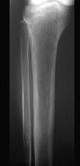

- 单项选择题下列哪项X线表现对甲状旁腺功能亢进症有诊断价值 ( )

D、骨膜下皮质吸收、颅骨斑点状脱钙